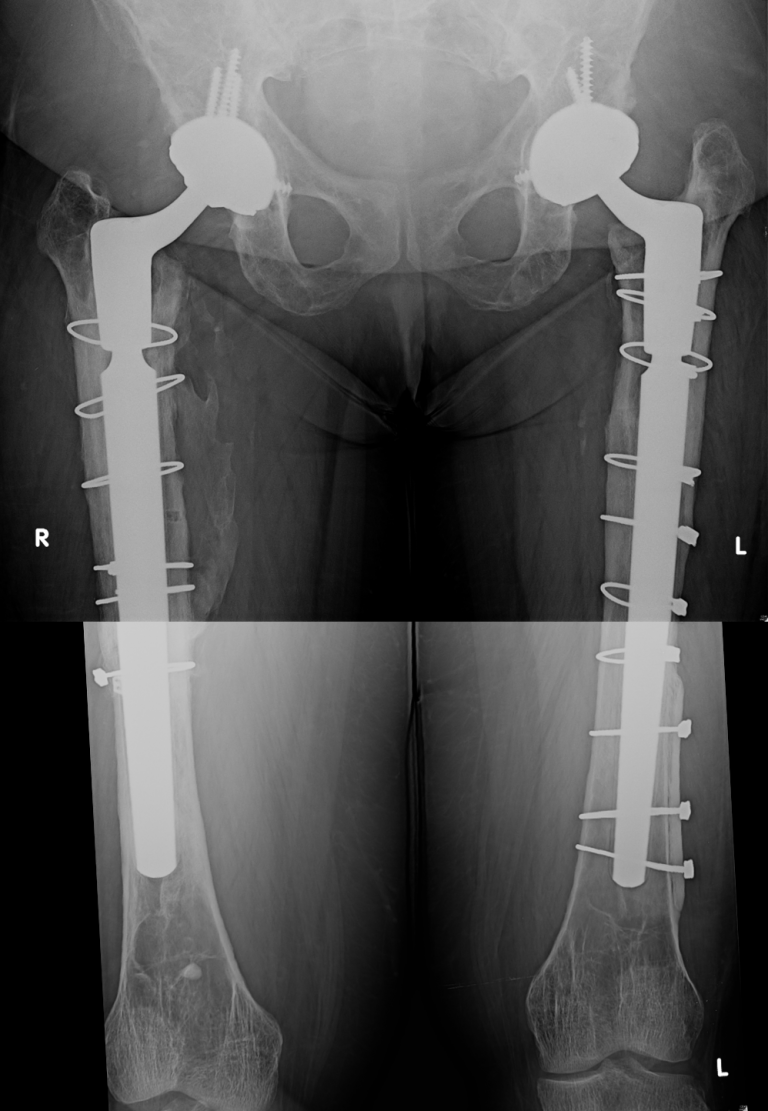

Bilateral THA Revision For Severe Varus Remodeling – Darwin Chen, MD

Bilateral THA revision for severe varus remodeling – Darwin Chen, MD www.darwinchenmd.com

varus tha bilateral darwin chen

varus bilateral severe remodeling tha darwin